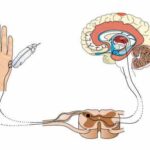

La intoxicación por bloqueadores beta-adrenérgicos es un fenómeno clínico complejo que se asocia a la administración excesiva o inadecuada de fármacos que actúan sobre los receptores beta-adrenérgicos del sistema nervioso…